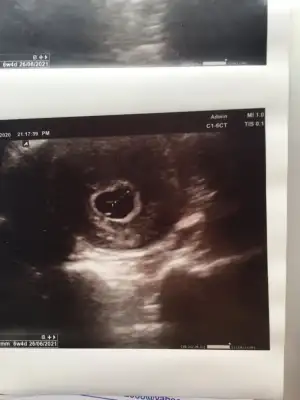

Sadece bu var 6+4 ondada sadece yol sacı gorunuyor bebek gorunmemişti7 haftalık varsa daha iyi olur aslında

Canım kıza benziyor sanki cinsiyeti öğrenince mutlaka yazın :)Sadece bu var 6+4 ondada sadece yol sacı gorunuyor bebek gorunmemişti

Eğer karındansa kız vajinalsa erkek ultrason

Vajinal ultrasyon tmm cnm tşklerEğer karındansa kız vajinalsa erkek ultrason